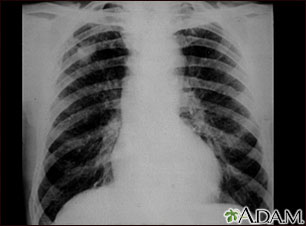

A chest x-ray is an x-ray of the chest, lungs, heart, large arteries, ribs, and diaphragm.

How the Test is Performed

You stand in front of the x-ray machine. You will be told to take a breath in and hold it when the x-ray is taken.

Two images are usually taken. You will first need to stand facing the machine, and then sideways.